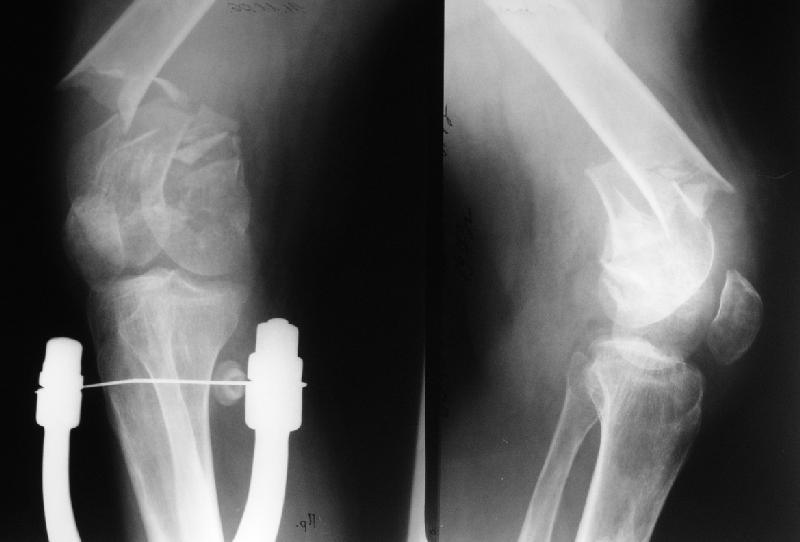

Такие дистальные мы предпочитаем делать антеградно. В дистальном овальном отверстии можно заклинить 2 винта третьим (см. картинку).

Для антгеградного сгибать особо не надо. Но после репозиции суставного

конца (открытой или закрытой) надо будет наложить дистрактор, а в нем

можно и согнуть, и разогнуть...

Больной поступил в клинику. Дополнительные сведения: диафизарный перелом (открытый)получил 5 лет назад - падение с 5 этажа. Лечился консервативно. Через год стал ходить без трости, хромоты не было, колено гнулось ( со слов больного),В принципе был удовлетворен своим состоянием. 1,5 месяца назад упал в подъезде (в состоянии алкогольного опьянения). Отказался от 2 группы инвалидности - просто не пошел на переосвидетельствование. Живет с мамой (пенсионерка).